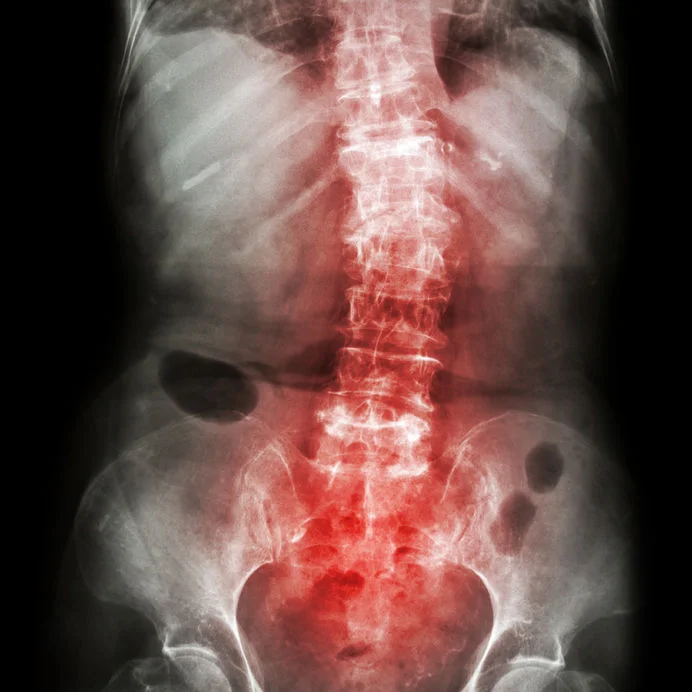

Scoliosis

Scoliosis is a term used to describe abnormal sideways curvature of the spine. One shoulder or hip may be higher than the other, giving indications that something is not quite right.

Kylie sees many children with scoliosis in her practice, and is thus experienced in the care of such patients. X-rays are sometimes deemed necessary after a full physical examination to determine the degree, angle and stage at which the scoliosis is at. Age also plays an important role on how this condition is cared for, this will be discussed with Kylie.

After examination, patient education is required to understand the cause and the treatment to follow. Care of this condition may require instruction on specific exercises, postural recommendations and chiropractic adjustments, referrals to concurrent spinal specialists will be made if deemed necessary for the best treatment possible.